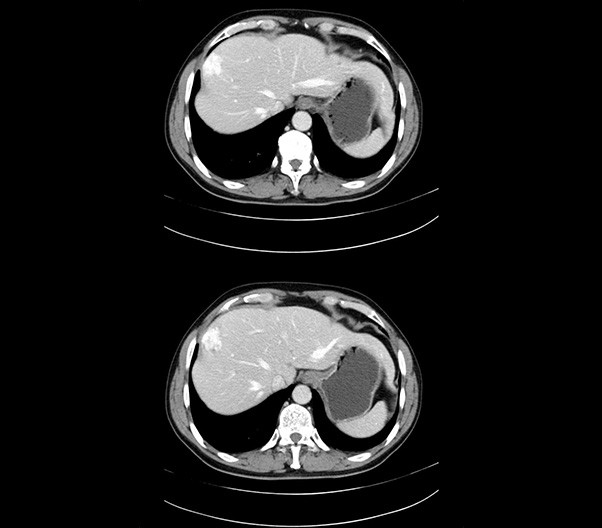

The 1024-pixel image matrix brings superior image clarity (0.6 mm slice thickness) and stimulates the early detection of small lesions, thus improving diagnostic reliance.

臨床畫(huà)廊